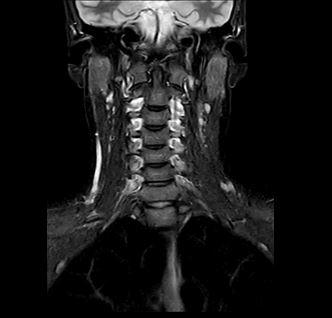

Beispiele von MRT-Hals Aufnahmen

Bei einer MRT des Halses können nahezu alle anatomischen Strukturen zwischen Kiefer und Schlüsselbein dargestellt werden. Die exakte Abbildung dieser Strukturen erlaubt es, Veränderungen frühzeitig zu erkennen und gezielt zu behandeln.